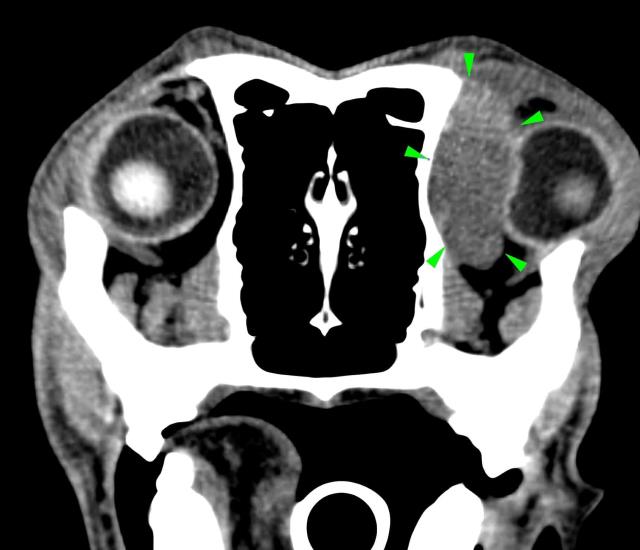

A 7-years-old Labrador was presented to with lethargy, anorexia and exophthalmos.

A CT scan of the head revealed the presence of a soft tissue space-occupying lesion of approximately 3 cm in diameter, arising from the orbital part of the left frontal bone (green arrowheads). The mass was laterally compressing the ipsilateral eye. A focal osteolytic process was observed at the level of the left zygomatic process of the frontal bone (light blue arrowhead).